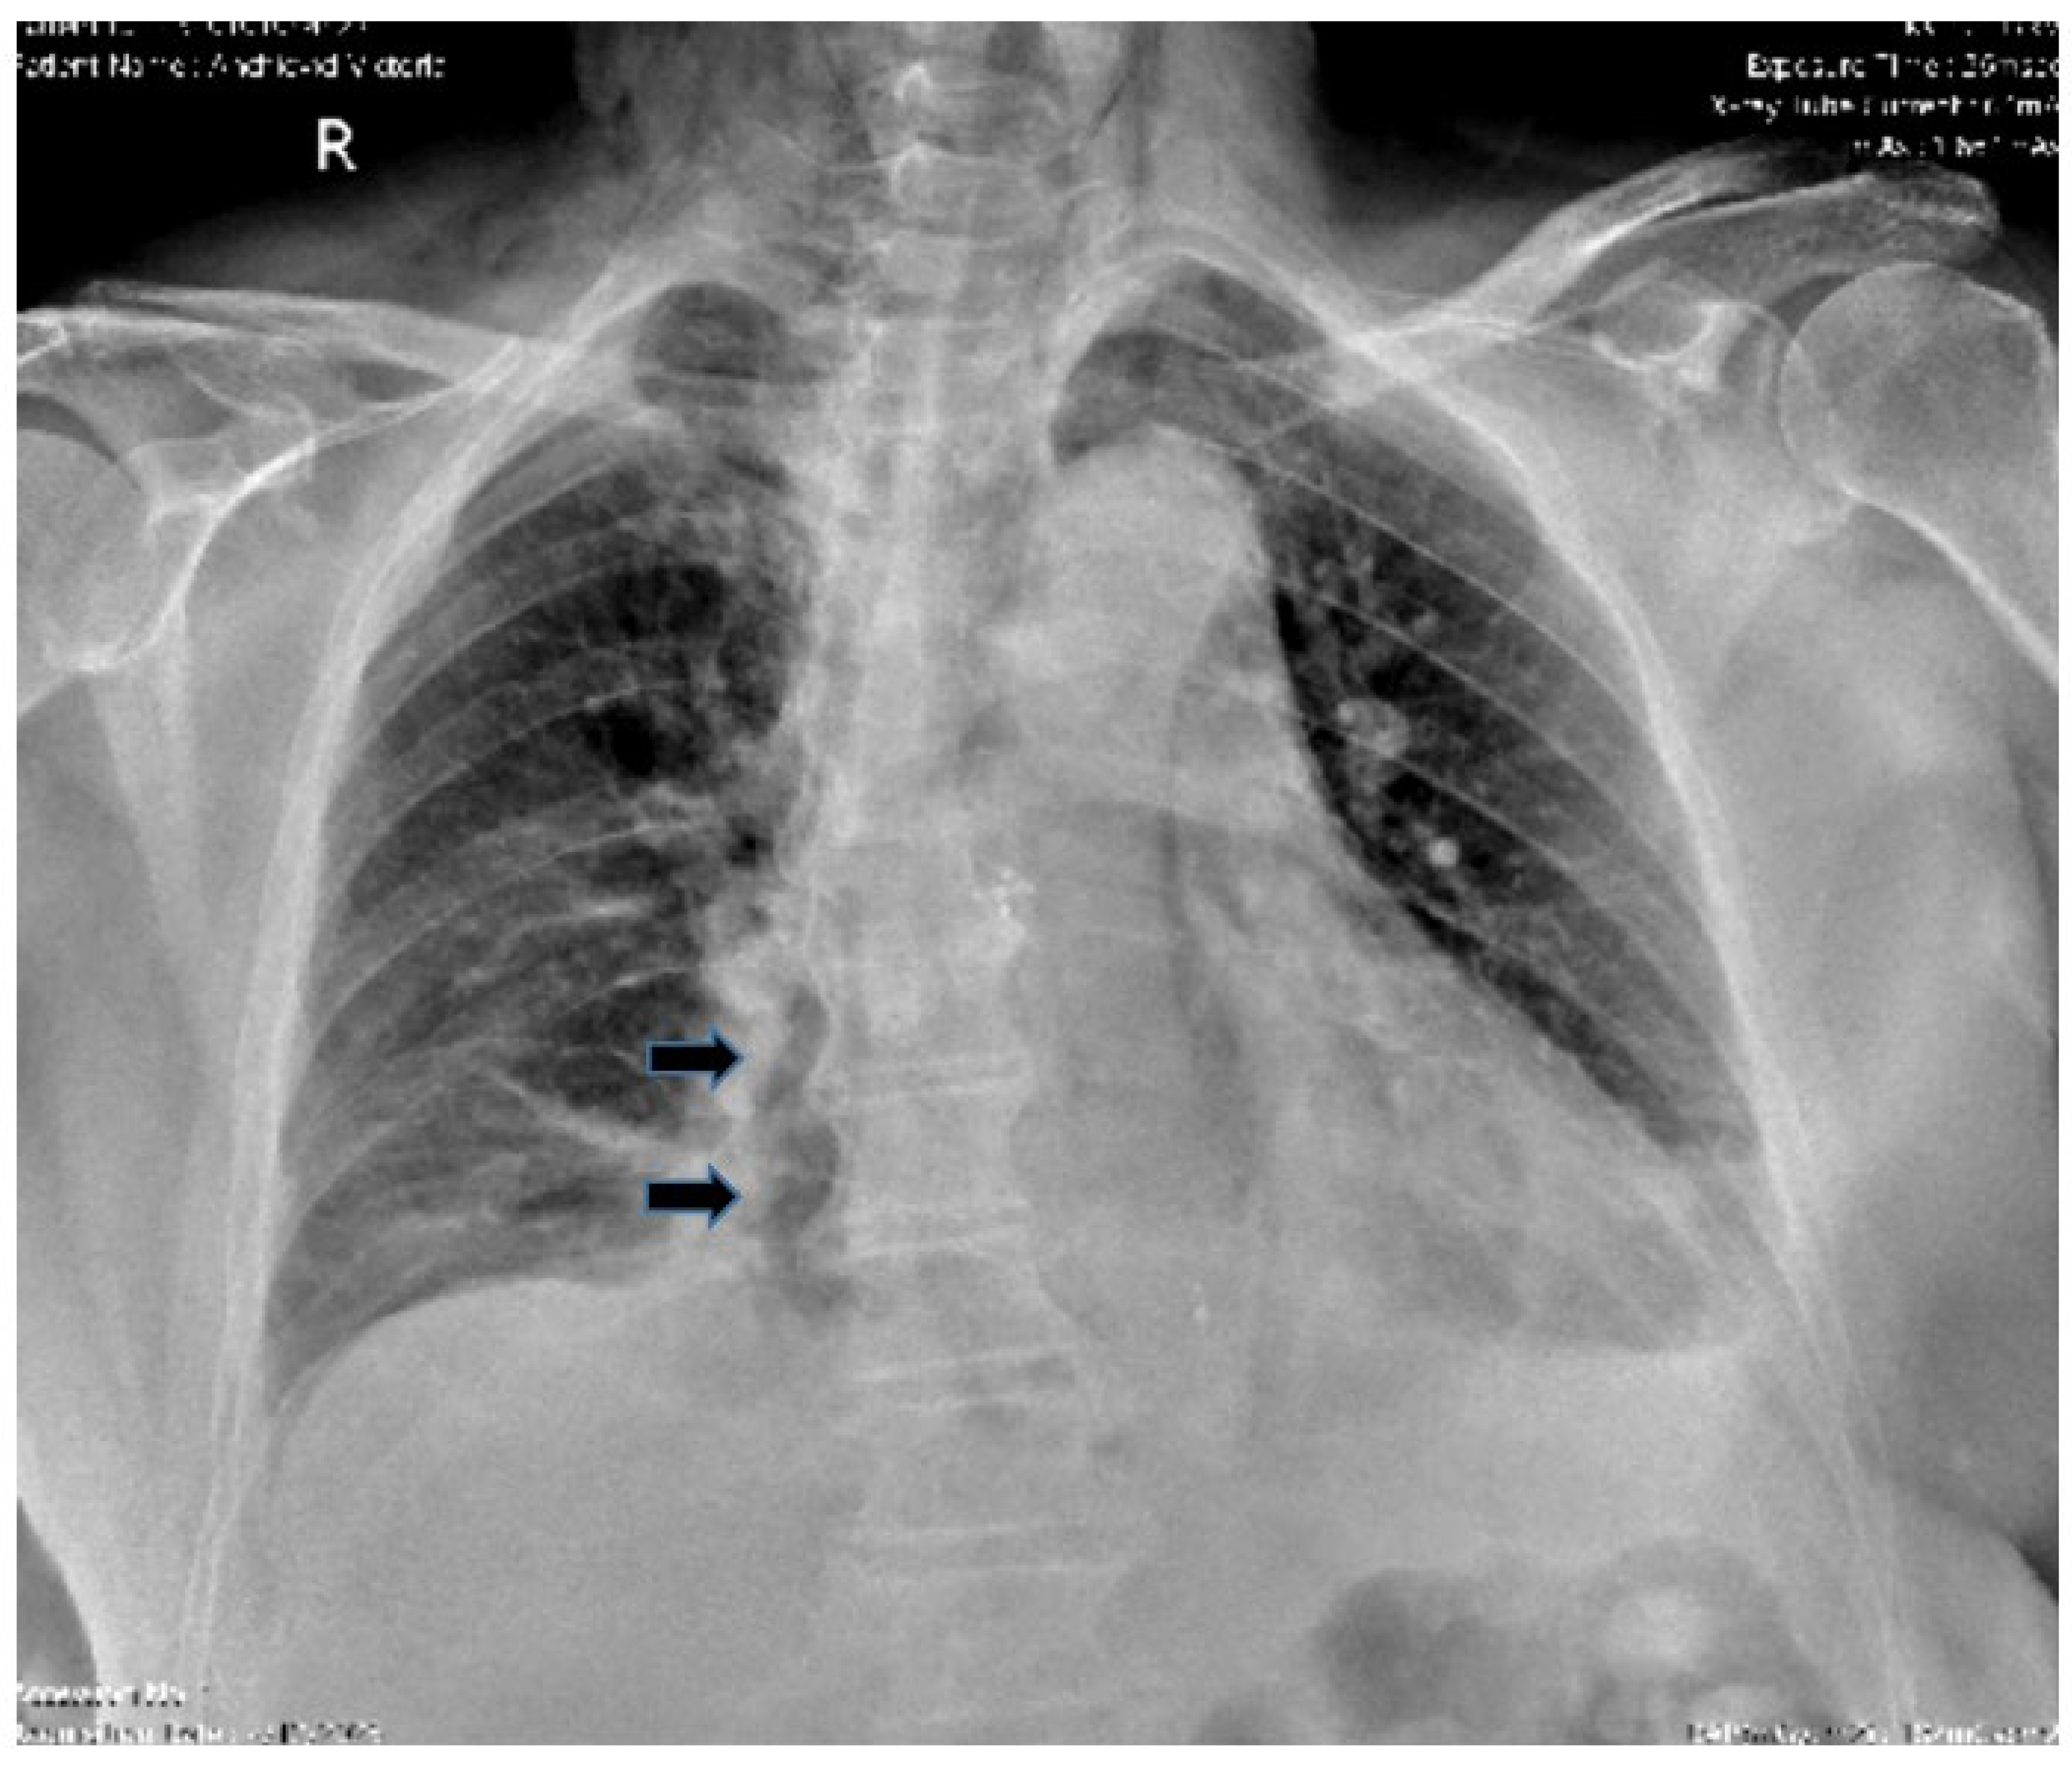

- Pneumomediastinum

- Pneumothorax (especially left-sided)

- Pleural effusion (especially left-sided)

- Localized periaortic gas

- Mediastinal fluid collections

- Thickened esophageal wall

- Gas within thoracic soft tissues, neck, or around major vessels

- Gas in the epidural space

- Pneumoperitoneum

- Gas in the retroperitoneal space

- Oral contrast extravasation from the esophageal lumen [10].